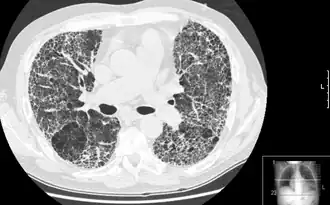

КТВР, демонстрирующая признаки пневмофиброза

Компьютерная томография высокого разрешения (КТВР) лёгких — медицинское исследование, применяемое для диагностики и оценки интерстициальных заболеваний лёгких. Метод использует специальные параметры КТ-сканирования, позволяющие оценить состояние лёгочной ткани и паренхима.